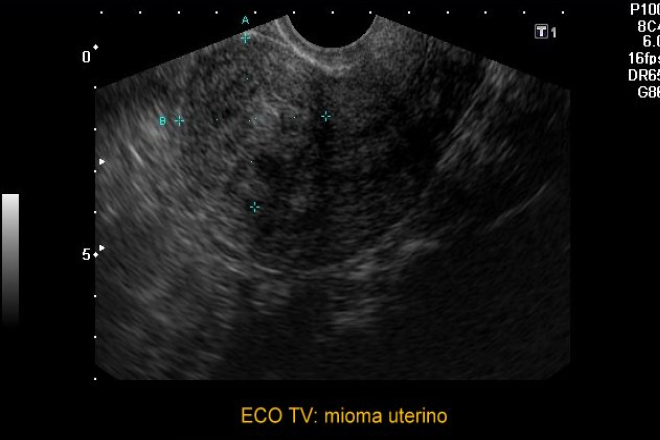

Son tumores benignos, redondeados o elipsoideos. Pueden presentarse de manera única o múltiple, en función del tipo de tejido que predomina. Reciben otras denominaciones: fibromiomas ricos en tejido conjuntivo, leiomiomas ricos en tejido muscular. Las manifestaciones clínicas son más tardías y se suelen relacionar con alteraciones de la menstruación más que con el tamaño del tumor. Pueden cursar de forma asintomática, pero también con dolor, metrorragias y favorecer la esterilidad, sobre todo si son múltiples. Los miomas se localizan en diferentes partes del miometrio, en la propia pared, inmediatamente por debajo del endometrio o en relación con la cubierta serosa.

En la miomatosis, la mayoría son tumores benignos que pueden presentar sintomatología temprana o tardía, pero que pueden ser muy molestos cuando se manifiestan. Ecográficamente se pueden diferenciar distintos tipos de miomas, entre los cuales pueden ser hipoecoicos, hiperecoicos e isoecoicos, estas distintas características son de gran relevancia para poder brindar un diagnóstico oportuno y un manejo temprano.